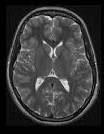

حال به تصویر مقابل توجه کنید و بگویید چه مىبینید.

چیز خاصى نمىتوان گفت، همان چیزى را مىبینیم که در عکس به چشم مىخورد و واقعاً نمىتوان گفت که این عکس شبیه چه چیزى است. شاید عکس مغز گردو است. دوست پزشک ما لبخندى مىزند و سپس مىگوید: عکس مغز است، اما نه مغز گردو بلکه مغز انسان؛ یک عکس MRI از مغز انسان. اما دوست پزشک ما نیز بیش از این نمىتواند درباره عکس صحبت کند و به نظر او براى اینکه بدانیم عکس مزبور چه چیزى درباره مغز فرد مىگوید باید آن را پیش متخصص عکسبردارى MRIببریم. با کمال تعجب به دوستمان مىگوییم چرا خودت درباره عکس نظر نمىدهى؟ وى مىگوید: این شیوه نوین، با عکسبردارى با اشعه ایکس متفاوت است. این نوع عکسبردارى به وسیله میدانهاى مغناطیسى انجام مىشود و وقتى من پزشکى مىخواندم، این شیوه مرسوم نبود و هیچ آموزشى در این مورد ندیده ام. تنها، متخصص عکسبردارى MRIاست که مىتواند درباره عکس نظر دهد. سپس عکس را به یک متخصص نشان مىدهیم. وى با دیدن عکس در مورد مناطق سیاه، روشن و خاکسترى عکس توضیحات مفصلى مىدهد، توضیحاتى که بسیارى از آنها را نمى فهمیم. اما سرانجام به این نتیجه مىرسیم که اگر مغز سالم بود، هنگام قرار گرفتن در حوزه مغناطیسى به شکل خاصى درمىآمد که این عکس آن شکل را ندارد. میزان تاریکى ها و روشنى هاى عکس به گونه اى است که نشان مىدهد شخص مبتلا به بیمارى آلزایمر است.

بخش اعظم تجربه هاى پیشین ما را آموزش هاى مدرسه و دانشگاه تشکیل مىدهد. و چون شیوه تصویربردارى MRI در هیچ جاى این تجربه قرار ندارد، نه تنها نمىتوانیم در مورد نوع بیمارى فرد اظهارنظر کنیم بلکه حتى نمىدانیم تصویر مزبور تصویر چه چیزى است.